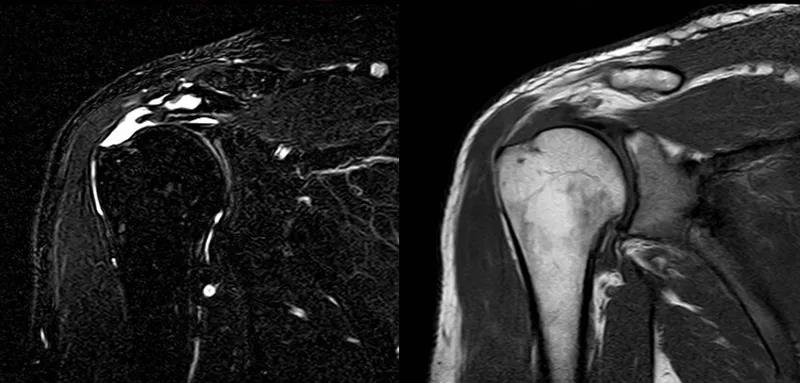

图21 斜冠状位(临床常用)a.T2,b.T1